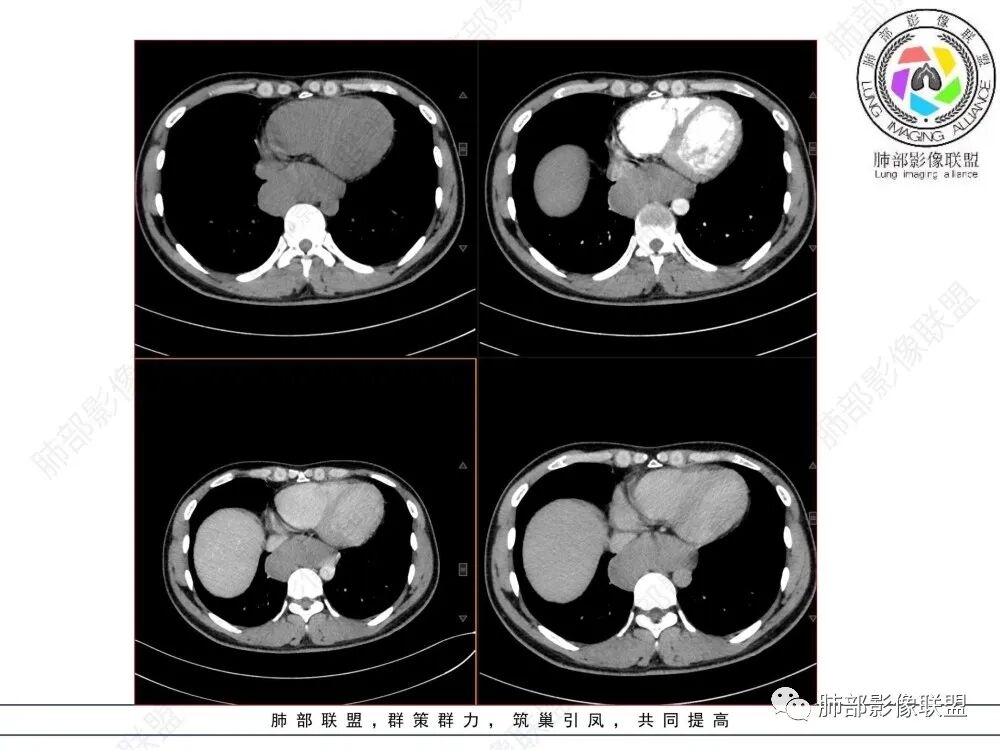

年轻男性,食管下段占位性病变长轴平行于食管,平扫密度尚均匀,增强轻度强化,MRI示T1、T2低信号,DWI低信号。考虑来源于食管,考虑平滑肌瘤或神经鞘瘤>间质瘤

定位后纵膈,这个位置,神经,淋巴,食管,轻微强化,T2低信号,弥散受限,考虑平滑肌瘤,鉴别神经原性。

平滑肌瘤(食管下段团块状肿块,环食管生长,分叶密度均匀,增强轻度强化。钡餐时食管受压移位,T1 T2 DWi低信号,病变来源于食管,考虑平滑肌瘤)

定位后纵膈,实性密度,增强轻度强化,T1等低信号T2低信号,弥散未受限。钡餐造影,食道及贲门管壁柔和,造影剂通过顺畅。考虑神经鞘瘤。鉴别食道平滑肌瘤。

轻度强化,等T1等T2,弥散不受限,密度及信号相对均匀,感觉后壁来源并食管受压推移,考虑平滑肌瘤。

T2低信号是关键,提示平滑肌细胞

食管平滑肌瘤是最常见的食管良性肿瘤,多见于男性,男女之比为2.6:1,高发年龄 30~60岁之间与食管癌相比,食管平滑肌瘤 的一个主要特点是病史相对较长,病情进展缓慢。病史最长者达10年余,平均 15.7个月,尽管病史较长,但大多数患者仍能进普食。食管平滑肌瘤的诊断一般比较容易,结合患者临床症状、食管造影及食管镜所见,一般均能得出正确诊断。食管造影主要为充盈缺损,病变与食管壁成锐角,粘膜线连续无破坏,管腔收缩扩张比较自如。钡餐造影敏感性高,但对食管壁间及食管周围情况难以判断。CT具有极高的密度分辨率,并且可以获得高质量的多平面重组图像,有利于食管壁间及食管周围情况的判断,表现为食管下段环绕管壁生长,偏心性或薄厚不均软组织密度肿块,密度均匀,内缘分叶状,管腔与正常食管壁构成不规则多角形扩张,增强动脉期无强化,多角度重建其病灶长轴与食管长轴不一致。由于食管壁在收缩状态下厚度约为5.6mm,扩张状态厚度不超过3mm,CT扫描时保持食管处于扩张状态可提高小病灶检出率。MR表现为T1加权等信号,T2加权稍高信号,可见高信号粘膜层,增强扫描轻度渐进性强化,密度均匀,无出血坏死。对于粘膜及周围脂肪间隙的判断具有明显优势。